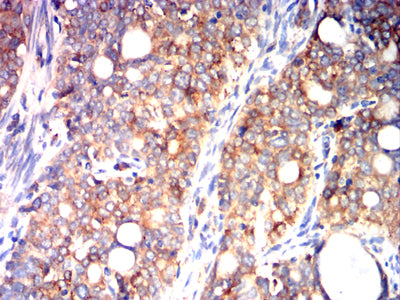

- Immunohistochemical analysis of paraffin-embedded human cervical cancer tissues using P4HB mouse mAb with DAB staining.

- Immunohistochemical analysis of paraffin-embedded human rectal cancer tissues using P4HB mouse mAb with DAB staining.

- Immunohistochemical analysis of paraffin-embedded human lung cancer tissues using P4HB mouse mAb with DAB staining.